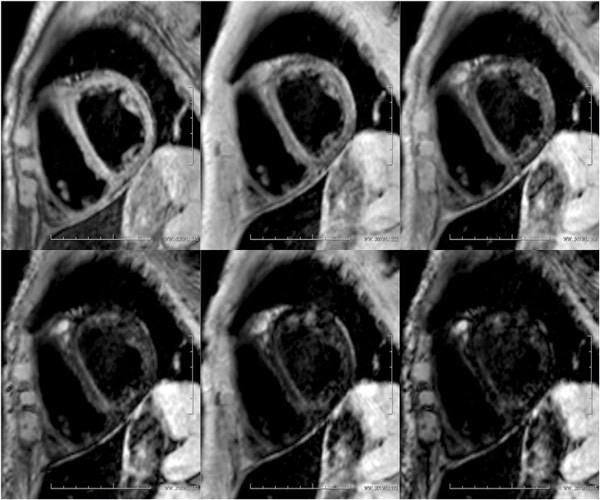

A CT examination of the liver was carried out that showed a pathologically elevated signal with average density 100 HU (Hounsfield units) (Fig. 2, Fig. 3), clearly consistent with iron accumulation in the liver. In the light of these findings, the probability of toxic overload in the liver was regarded as so great that the risk associated with a liver biopsy was not justified. An MRI cor was also carried out at the university hospital, where a T2-weighted image showed maximum pathological values of < 10 ms (> 20 ms), consistent with iron accumulation in the myocardium (Fig. 4). We found no validated method of measuring iron accumulation in the pancreas and thyroid.

Figure 4  T2-weighted MR cor images show (from top left to bottom right) iron accumulation in the myocardium. Pathological…

Figure 4 T2-weighted MR cor images show (from top left to bottom right) iron accumulation in the myocardium. Pathological values are < 20 ms. The septum is measured, a curve constructed and the time under the curve calculated. The patient's value was < 10 ms, i.e. pathological